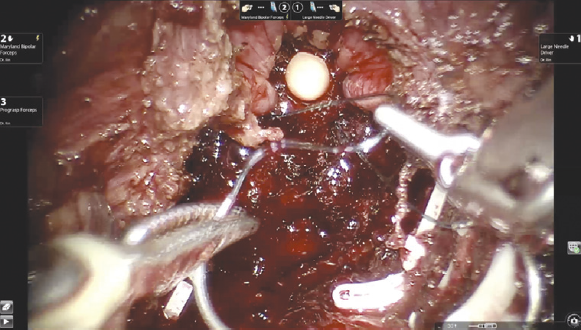

Вскрытие париетальной брюшины в проекции шейки мочевого пузыря. Операция выполняется трансперитонеально, расположение роботических троакаров повторяет таковое при традиционном доступе. Ассистентские 12- или 5-миллиметровые порты также устанавливаются стандартно: параректально справа на 2–3 см выше оптического порта и на 6–8 см латерально от правого роботического порта соответственно. На первом этапе происходит вскрытие париетальной брюшины. В отличие от традиционного доступа, инцизия производится в проекции шейки мочевого пузыря, а не его верхушки. Для лучшей визуализации третьим роботическим инструментом осуществляется тракция задней стенки мочевого пузыря вверх. Выделение семявыносящих протоков и семенных пузырьков (рис. 1). Этот этап операции выполняется сразу после вскрытия париетальной брюшины. Техника диссекции семявыносящих протоков и семенных пузырьков не отличается от стандартной. Основным фактором, обеспечивающим техническую сложность этого этапа, является небольшой объем операционного поля и невозможность выполнения широких тракций семенных пузырьков и самой предстательной железы, которая на данном этапе остается выделенной лишь на небольшой поверхности ее основания. Выделение задней поверхности простаты и сосудисто-нервных пучков (рис. 2), как и при традиционном доступе, происходит после этапа выделения семенных пузырьков. Уровень нервосбережения определяется на основании стадии опухолевого процесса. Для доступа к заднелатеральным отделам предстательной железы выполняется частичная латеральная диссекция пузырно-простатических мышечных волокон. Диссекция шейки мочевого пузыря (рис. 3) выполняется в направлении снизу вверх и является одним из самых сложных шагов этой операции. На этом этапе в наибольшей степени проявляется преимущество свободно изгибающихся на концах роботических инструментов. Для лучшей визуализации используется развернутая наверх (30°) оптика. Шейка мочевого пузыря вскрывается по задней поверхности, уретральный катетер извлекается, после чего рассекается передняя ее поверхность. Диссекция дорзального сосудистого комплекса производится тупым и острым путем без предварительного прошивания и перевязывания. После выделения верхушки простаты железа отсекается от уретры. На этом этапе при необходимости производится прошивание элементов дорзального комплекса. На рис. 4 представлено ложе удаленной предстательной железы. Наложение пузырно-уретрального анастомоза (рис. 5) начинается с передней его стенки на 12 ч условного циферблата. Анастомоз выполняется с использованием самозатягивающихся нитей. Сложность этого этапа обусловлена, в основном, непривычной визуализацией. Ввиду того, что мобилизация мочевого пузыря не производилась, сопоставление слизистой уретры и мочевого пузыря происходит без видимого натяжения, поэтому усиления соустья с помощью дополнительной реконструкции не требуется. При необходимости выполняется задняя пластика шейки мочевого пузыря. Последним этапом производится установка дренажа к зоне анастомоза и ушивание париетальной брюшины.

Рис. 4. Ложе удаленной предстательной железы

Fig. 4. The bed of the removed prostate gland